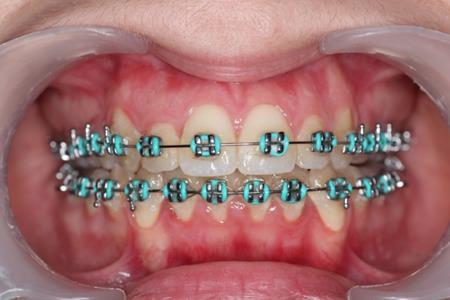

In this case the implants were loaded after one week with a 100-150 force using an elastic chain.

The intrusion rate obtained was 0,5-1 mm per month without root resorbtion or vitality problems.

Figure 5.Intraoral photography after the mini-implant activation

Figure 7.Clinical situation after intrusion with orthodontic implants.